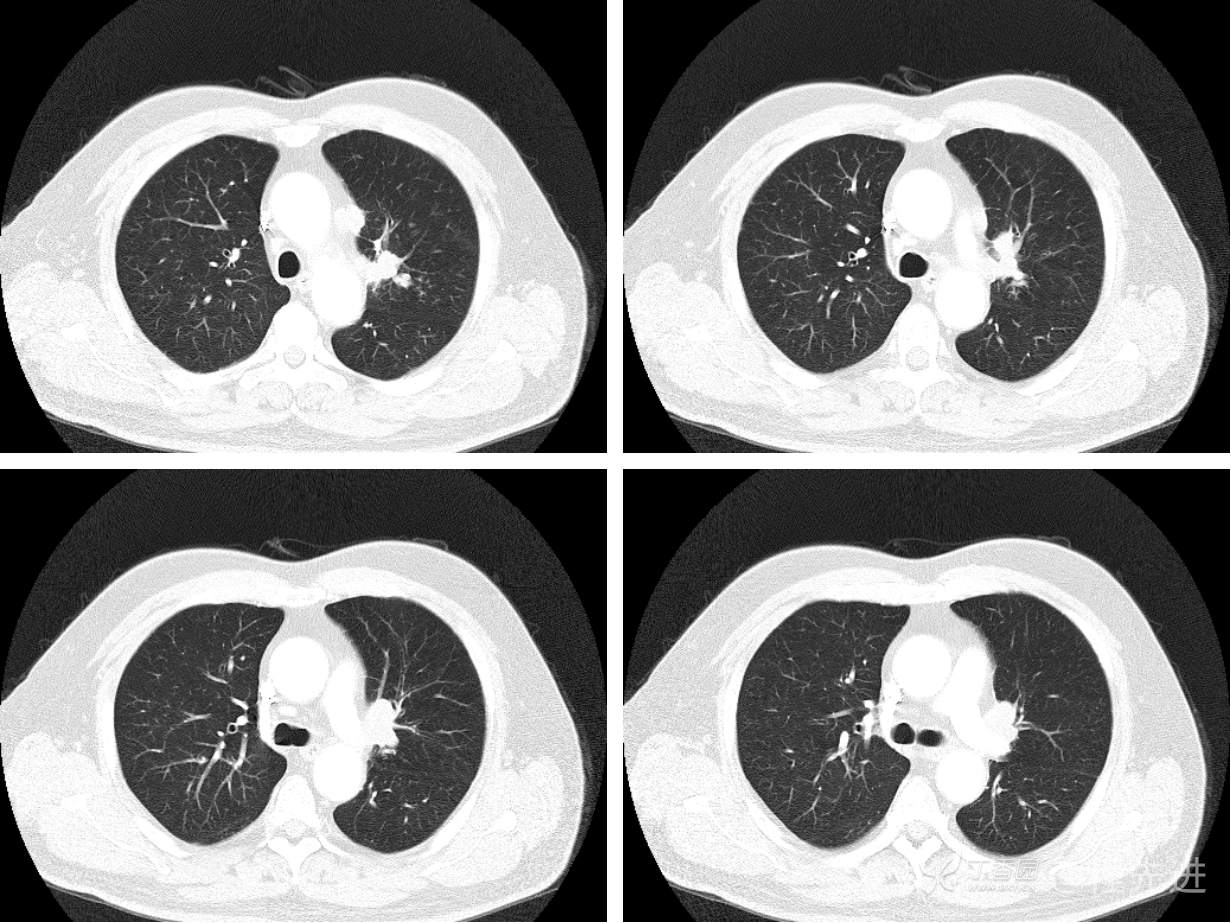

现病史概要:患者入院前约半月无明显诱因下出现咳嗽、胸闷症状,无明显发热症状,咳少量白痰,无明显咯血、喘息、头晕等不适,就诊我院查胸部CT示上纵膈肿物,左肺上叶支气管内肿物,现为行进一步治疗收入胸外科,患者近来饮食睡眠尚可,二便如常。